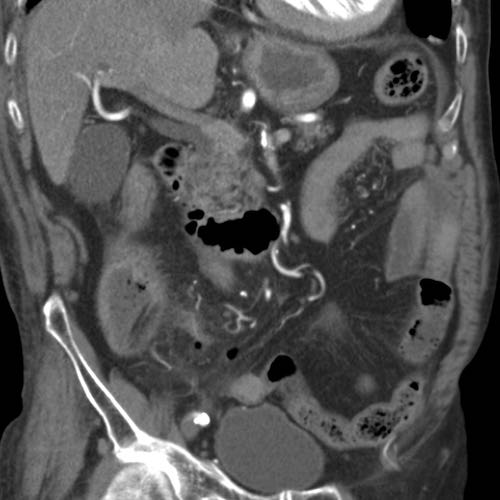

Bệnh nhân nữ 74 tuổi nhập viện với đau bụng dưới sâu kéo dài 3 tuần. Xét nghiệm: bạch cầu 15, CRP 150. Bệnh nhân có tiền sử nhiều lần phẫu thuật phụ khoa.

CT được thực hiện và phát hiện một dị vật dạng xương, với cả hai đầu đều có vẻ xuyên thủng đại tràng sigma.

Siêu âm qua đường âm đạo xác nhận dị vật đi xuyên qua lòng đại tràng sigma, do đó có thể lấy dị vật qua nội soi đại tràng.

Trong quá trình nội soi, xương gà phải được bẻ làm hai phần để lấy ra an toàn. Bệnh nhân hồi phục tốt với sự hỗ trợ của kháng sinh.